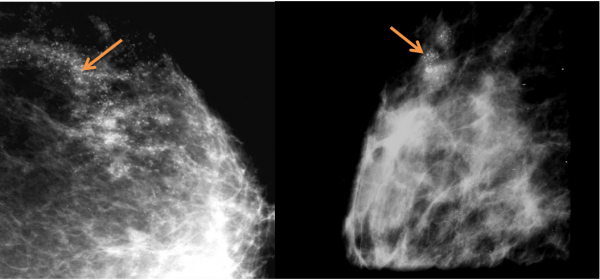

בממוגרפיה ניתן לראות הסתיידויות זעירות במרבית החולות, כאשר המאפיין את השאתות הללו הן הסתיידויות קוויות (ליניאריות), או קבוצות גדולות של 20 הסתיידויות ויותר בקבוצה. ההסתיידויות הן בגדלים שונים ובסמיכות שונה (תצלום 35.12). לעתים ניתן לראות סמיכות רקמתית או גוש זעיר. רק בחלק קטן מהחולות ניתן למשש גוש בשד בנוסף לממצא הממוגרפי.